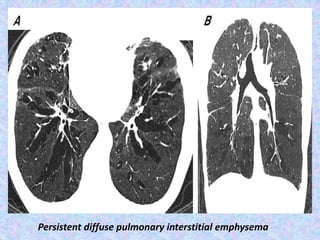

Persistent diffuse pulmonary interstitial emphysema

Persistent diffuse pulmonaryinterstitial emphysema

Pulmonary interstitial emphysema.

Pulmonary interstitial emphysema (PIE) refers to the abnormal location of air

within the pulmonary interstitium and lymphatics. It typically results from rupture

of overdistended alveoli following barotrauma in infants who have respiratory

distress syndrome. Interstitial emphysema can also occasionally be incidentally

detected in adults.

Radiographic features

Plain film - chest radiograph shows bubbles (round) or streaky (linear)

radioculencies in the interstitium radiating from the hilum . Affected segment is

often hyperexpanded and static in volume on multiple radiographs. Patients may

have pneumothorax, pneumomediastinum, or pneumopericardium in supine

patients, pneumomediastinum is evident by the sharp mediastinum sign

CT chest

shows cystic radioculencies in affected segment may characteristically show a line

and dot pattern with pulmonary arterial branches surrounded by radiolucent air

may help differentiate persistent PIE from a hyperlucent mass such as congenital

lobar emphysema, congenital pulmonary airway malformation (CPAM)

allows better visualization of a pneumothorax or pneumomediastinum

if incidentally detected in adults, it may appear as perivascular lucent or low-

attenuating halos and small cysts.